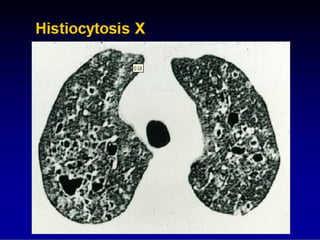

Other forms of

DPLD, eg, LAM,

HX, etc